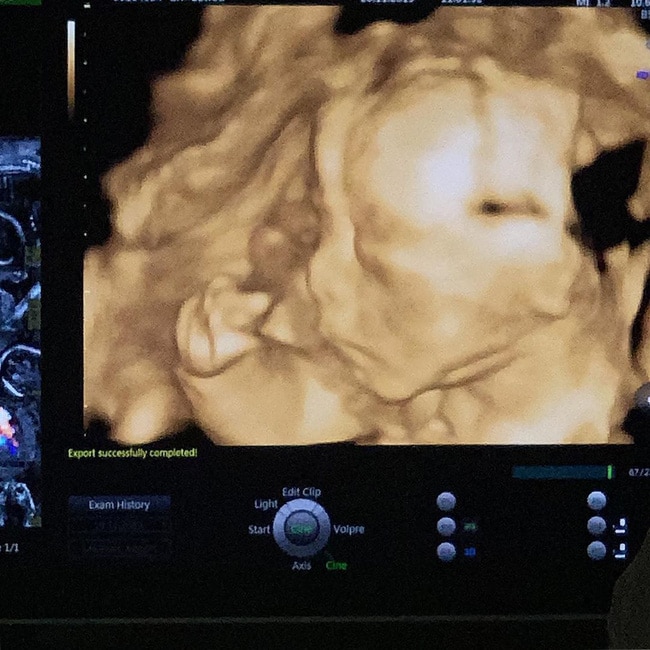

Kết quả siêu âm được Joyce Phạm chia sẻ 9 tuần trước ngày sinh